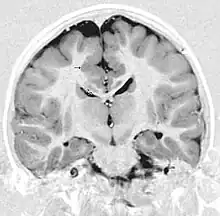

- Radiological findings (MRI) demonstrated symmetric generalized polymicrogyria with decreasing anterior-posterior gradient, most prominent in frontoparietal cortex.[5]

- Numerous gyrus on the cortex

- Small gyri and sulci

- Thin cortex

There are different tests or methods used to determine GPR56 expression or visuals of the brain to analyze the specific sections that are affected. These tests for example, using animals such as mice, RNAi, Behavioral assay, Electron microscopy, CT scan, or MRI demonstrate different results that concludes an affected BFPP patient.[16] MRI's reveal either irregularity to the cortical surface suggestive of multiple small folds or an irregular, scalloped appearance of the gray matter-white matter junction.

Neuroimaging The diagnosis of polymicrogyria is typically made by magnetic resonance imaging (MRI) since computed tomography (CT) and other imaging methods generally do not have high enough resolution or adequate contrast to identify the small folds that define the condition. The cerebral cortex often appears abnormally thick as well because the multiple small gyri are fused, infolded, and superimposed in appearance.[5]

Neuropathology Gross neuropathologic examination reveals a pattern of complex convolutions to the cerebral cortex, with miniature gyri fused and superimposed together, often resulting in an irregular brain surface. The cortical ribbon can appear excessively thick as a result of the infolding and fusion of multiple small gyri.[5]